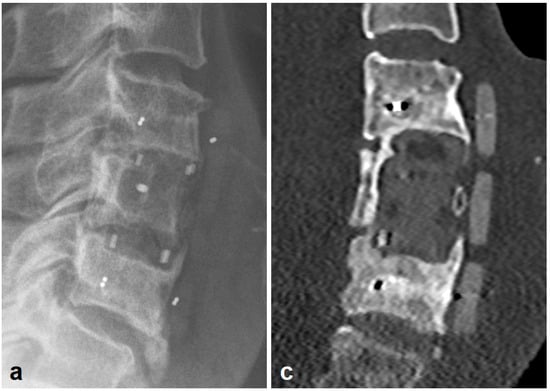

3.2. Radiologic Outcomes